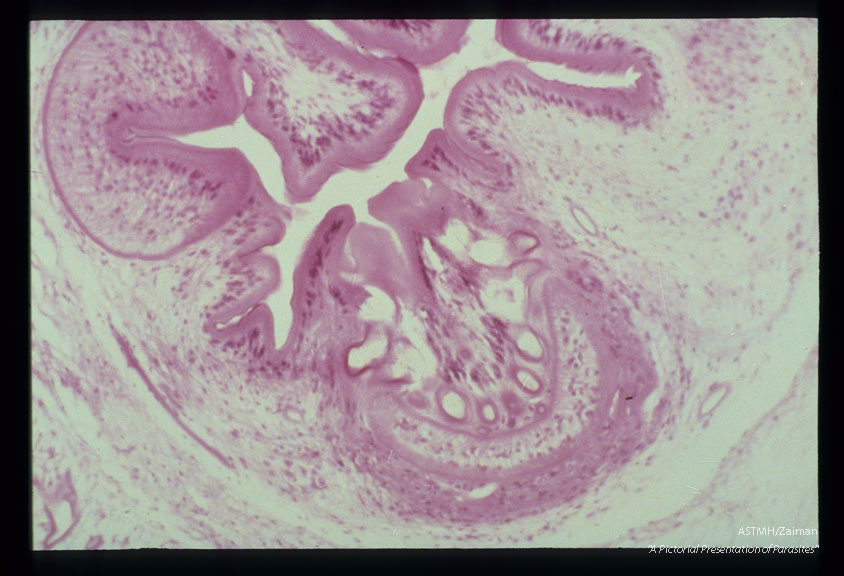

Photomicrographs of a subcutaneous nodule in a patient.

Taenia solium

Description: Photomicrographs of a subcutaneous nodule in a patient.